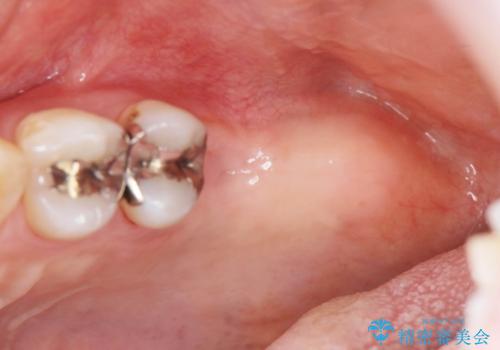

上顎奥歯のインプラント治療

- 奥歯を失い咬合機能の回復のためインプラント治療を希望され来院されました。

しっかりと食事ができるようになり、当院のインプラント治療に満足いただくことができました。